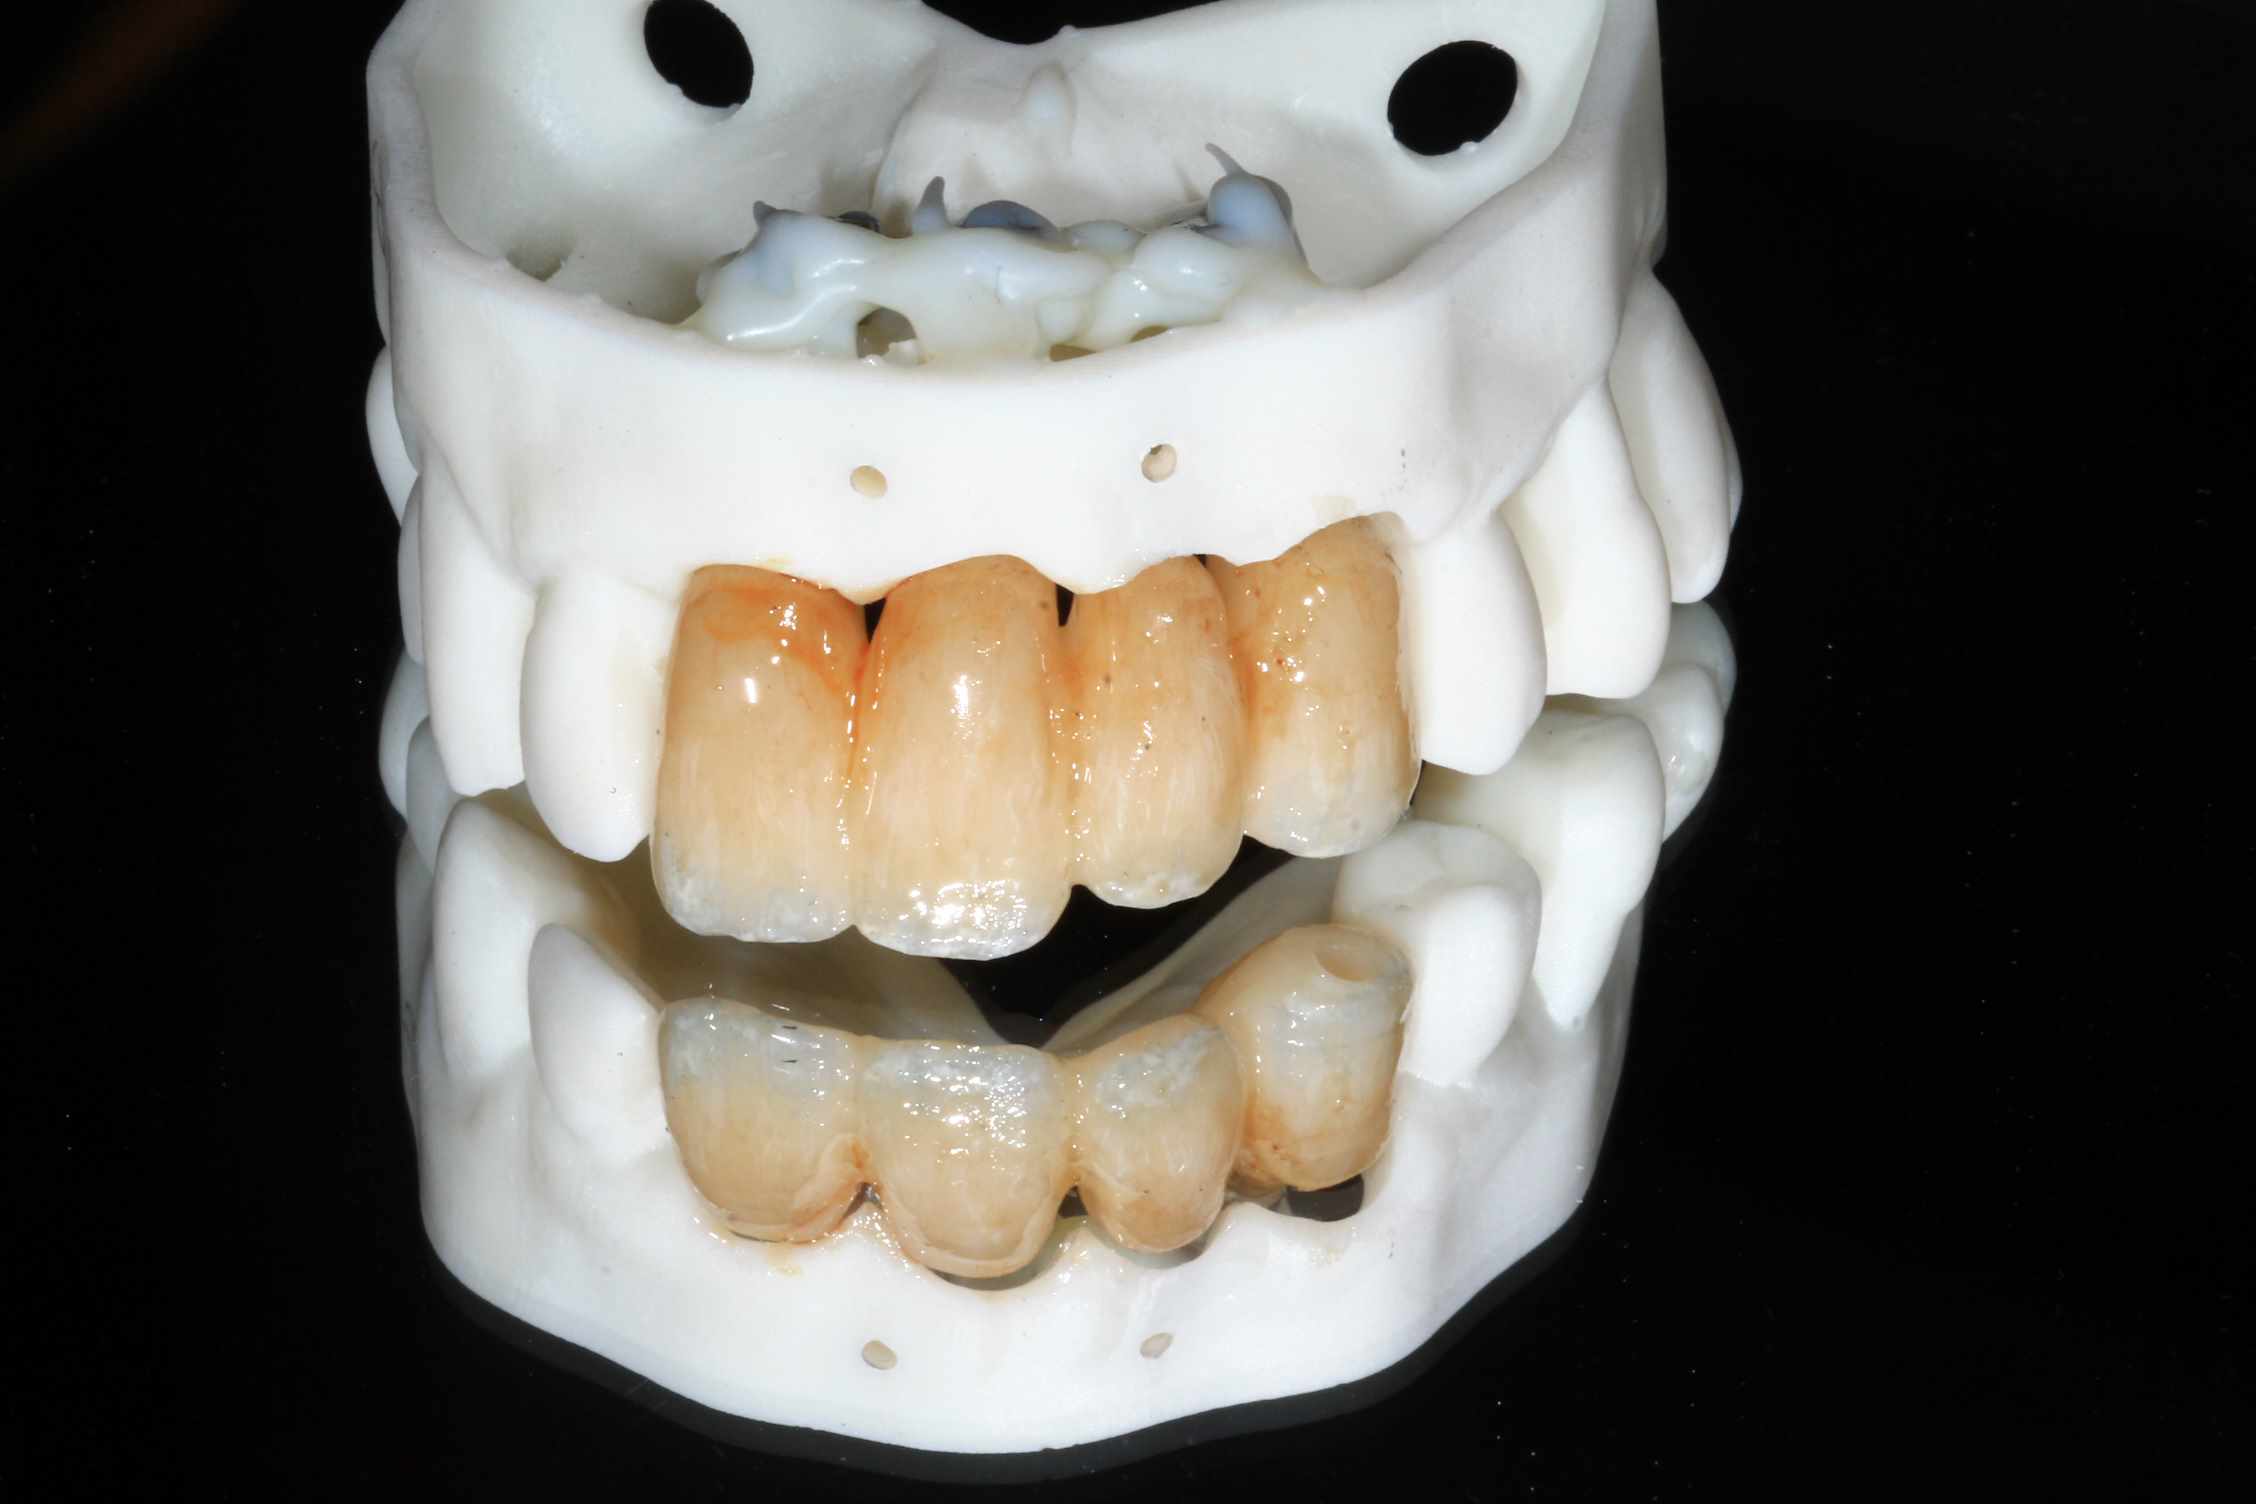

Mais celui la est tout chaud ( de vendredi dernier ) et j'ai regarder le temps que j'ai mis ( beaucoup plus complexe, donc plus long ). on va l'appeller Cas 2.

3 h de planif, modélisation du guide, puis 2 h environ pour la simulation de la chir , le modelisation et l'impression du bridge, qui tombe pile, zero retouche occlusale.

simulation de la chir. scan, matching des elements avec medit design, finition du bridge dana meshmixer.

Resultat a une semaine, 3 mois et bridge Full zircone katana maquillé MyIO rosensrew.